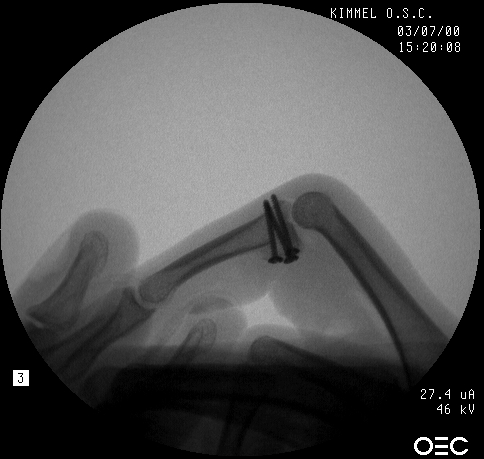

In the operating room, the crushed bone is removed and provisional fixation of the volar graft is obtained with Kirschner wires.

These wires are then replace, one at a time with micro screws.